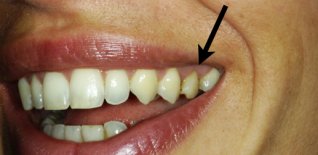

Impianto singolo a carico immediato

Frattura del secondo premolare superiore.

Dopo l'estrazione viene eseguito l'impianto e l'elemento dentario immediato.